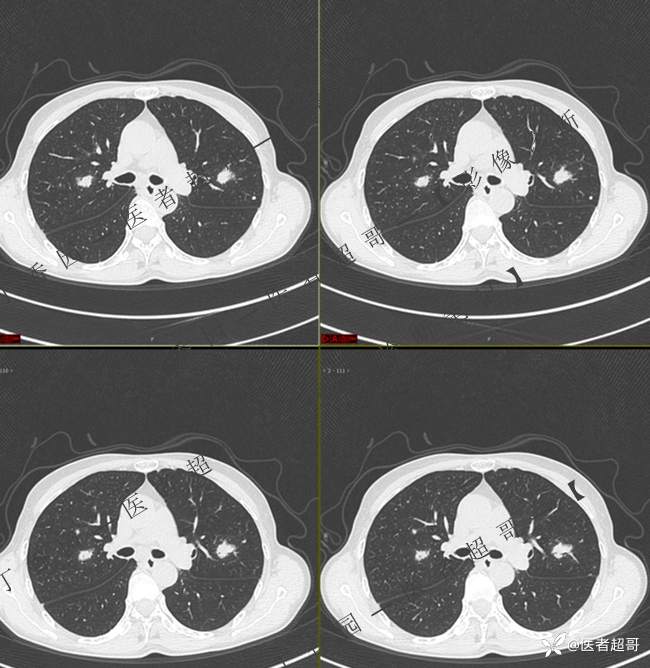

第一次检查